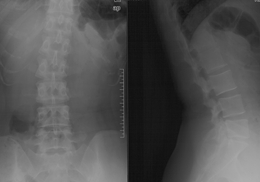

高* 女,腰痛伴左臀部疼痛麻木,左足麻木半月。

查体:腰5骶1棘间及左棘旁压痛、叩痛明显,疼痛向左臀部放射,左臀部外侧及左足底皮肤感觉减退,左跟腱反射减弱,左侧直腿抬高试验阳性(40°),加强试验阳性。

腰椎MRI示:L5S1椎间盘突出,左侧神经根受压。

(图)术前X线片